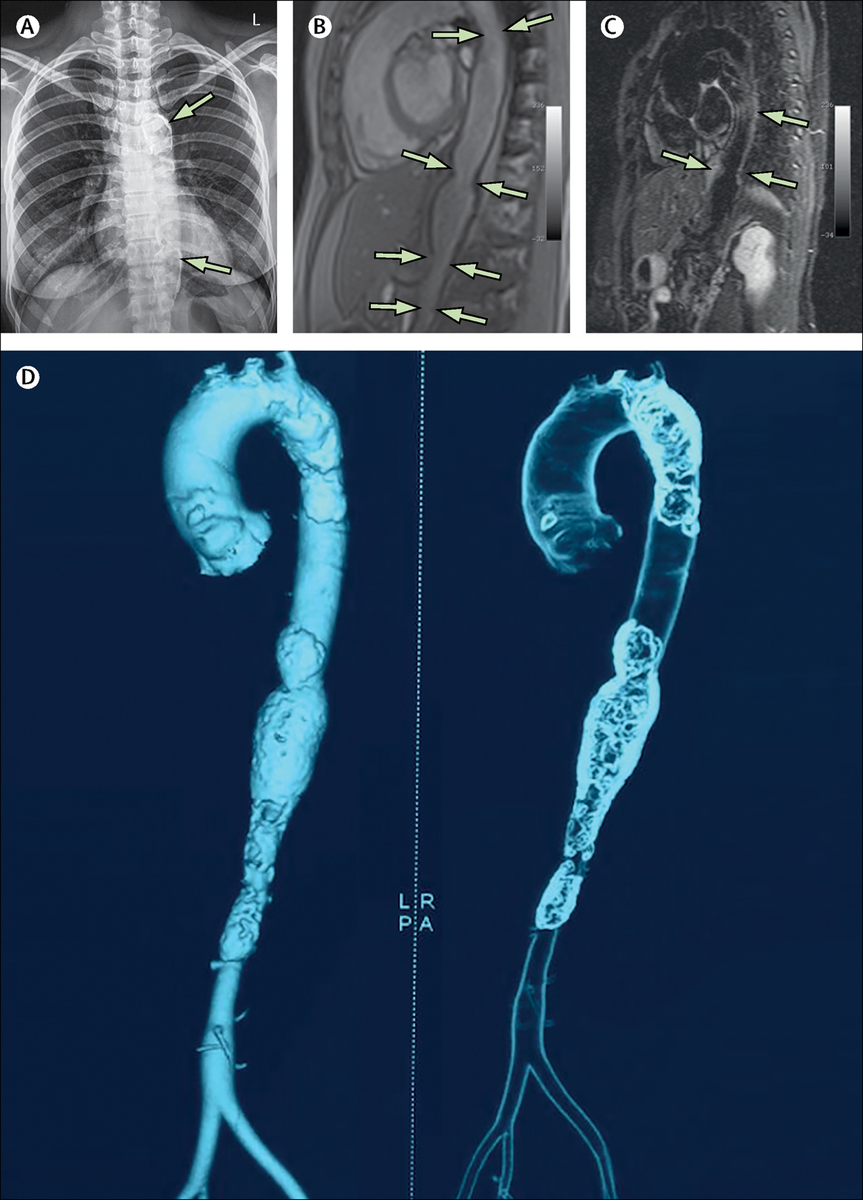

Болезнь Такаясу, конечно, не то, о чем написано в нашем материале, но выглядит она, куда более наглядно для неспециалиста, пусть это будет моделью. Артерии при экстремальном сердечно-сосудистом старении буквально каменеют.

Aortic calcification in longstanding, undiagnosed Takayasu arteritis